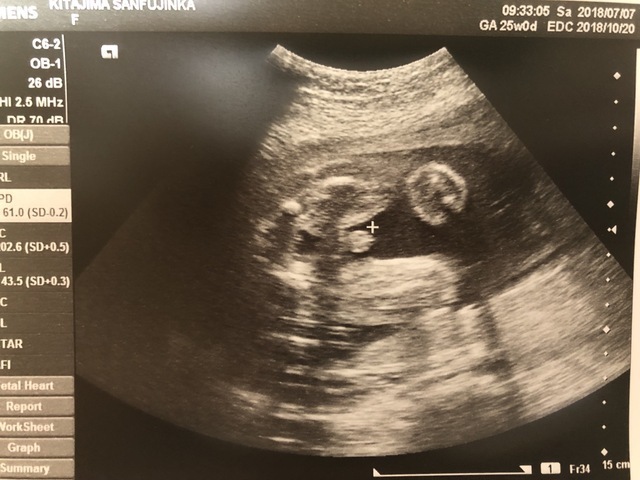

25週0日(25w0d・男の子)|ち75 さん(32歳)

エコー写真撮影時のエピソード:

昔にバンドのボーカルをやっていたり、歌うことも音楽を聴くことも好きなので、妊娠中は今まで行こうと思って行けなかったバンドのライブに行く事にしました。

ライブ中も胎動が激しい曲や何も動かない曲など、好みがあるみたいで面白かったです。エコー写真は歌っている様に、口をパクパクしていた時の息子です。